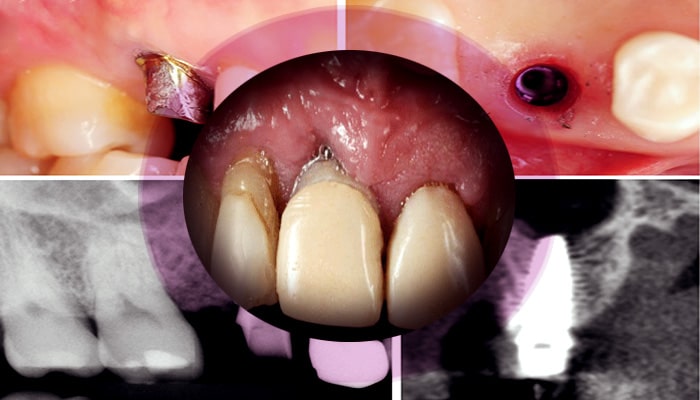

دکتر سمیرا حاج حیدری ، متخصص ایمپلنت دندان، با بهره‌گیری از تکنولوژی‌های پیشرفته و متدهای نوین، فرایند ایمپلنت گذاری را به شیوه‌ای کارآمد و بی‌دردسر انجام می‌دهد. در مراحل ابتدایی، دکتر حاج حیدری با ارزیابی دقیق وضعیت دندان‌ها و لثه‌ها، طرح درمانی متناسب با نیازهای هر بیمار را تهیه می‌کند. سپس با استفاده از تصاویر رادیوگرافی و اسکن‌ های سه‌بعدی، محل دقیق قرارگیری ایمپلنت را مشخص کرده و با دقت و مهارت بالا، ایمپلنت را در استخوان فک قرار می‌دهد. این روش نه تنها تضمین‌ کننده موفقیت بالای درمان است، بلکه زمان بهبودی را نیز به حداقل می‌رساند.

ایمپلنت‌ دندان فرآیندی پیچیده و چند مرحله‌ای است که توسط دکتر سمیرا حاج حیدری، متخصص و دکتر ایمپلنت‌ دندان، به دقت انجام می‌گیرد. در مرحله نخست، بیمار به یک مشاوره جامع دعوت می‌شود تا نیازها و نگرانی‌های او بررسی شود. پس از تصویربرداری های لازم و ارزیابی وضعیت دهان و دندان، برنامه درمانی مناسب تنظیم می‌شود. در مرحله بعد، عمل جراحی برای قرار دادن ایمپلنت در فک انجام می‌شود. این مرحله به دقت و مهارت بالایی نیاز دارد و دکتر حاج حیدری با استفاده از تکنیک‌های پیشرفته، ایمپلنت را در محل مناسب قرار می‌دهد.

پس از قرارگیری ایمپلنت، دوره‌ای از بهبودی آغاز می‌شود که در خلال آن، استخوان فک به تدریج با ایمپلنت جوش می‌خورد و ثبات لازم فراهم می‌شود. پس از این مرحله، پروتز دندان، که می‌تواند تاج یا سایر انواع دندان‌های مصنوعی باشد، بر روی ایمپلنت نصب می‌شود. در نهایت، دکتر سمیرا حاج حیدری با پیگیری‌های منظم و مشاوره‌های لازم، اطمینان حاصل می‌کند که بیمار از نتیجه نهایی راضی باشد و عملکرد و زیبایی دندان‌ها به بهترین نحو ممکن حفظ شود.